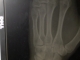

The injury: A broken bone in my left hand, just below the fourth finger. I went swimming in rough surf, got knocked over, and broke a small but apparently vital bone in my hand. Below the task is documented in picture form.

3. The potential image manipulation when dealing with X-rays is AWESOME to any gadget appreciator. You can zoom in, play with contrast... really if it hadn't been my own bones I'd been looking at I would have found it entirely fun.